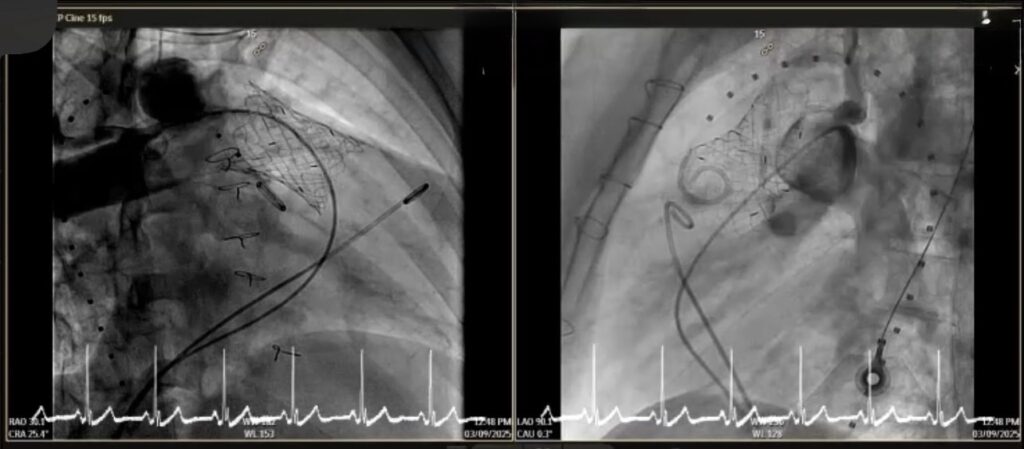

คณะแพทยศาสตร์ มช. สร้างความสำเร็จทางการแพทย์ ด้วยการรักษาโรคลิ้นหัวใจพัลโมนิกรั่ว (Pulmonary valve regurgitation) ผ่านสายสวน ในผู้ป่วยหญิงไทย อายุ 22 ปี ที่มีประวัติผ่าตัดรักษาภาวะ Tetralogy of Fallot มาก่อน และมีอาการของลิ้นพัลโมนิกรั่วรุนแรง

การใส่ลิ้นหัวใจพัลโมนิกเทียมผ่านสายสวนหัวใจ (Transcatheter pulmonary valve implantation; TPRI ) ในครั้งนี้ ทำผ่านทางหลอดเลือดดำใหญ่ บริเวณขาหนีบ จึงไม่ต้องผ่าตัดเปิดทรวงอก โดยกระบวนการรักษาและพักฟื้นผ่านไปได้ด้วยดี ไม่พบภาวะแทรกซ้อน ผู้ป่วยสามารถออกจากโรงพยาบาล 2 วันภายหลังการรักษา นับเป็นหนึ่งในความก้าวหน้าของนวัตกรรมการแพทย์เพื่อใช้รักษา ลดความเสี่ยงของภาวะแทรกซ้อนต่างๆ รวมถึงยกระดับคุณภาพชีวิตของผู้ป่วยได้

การรักษาผ่านทางสายสวนครั้งนี้ได้รับความร่วมมือจากสหสาขาวิชาชีพ อาทิเช่น ศัลยแพทย์โรคหัวใจ ทรวงอก และหลอดเลือด กุมารแพทย์โรคหัวใจ อายุรแพทย์โรคหัวใจ วิสัญญีแพทย์ รังสีแพทย์ นักเทคโนโลยีหัวใจและทรวงอก รังสีแพทย์และนักรังสีการแพทย์ เจ้าหน้าที่และพยาบาลห้องสวนหัวใจ ห้องผ่าตัดศัลยกรรมทรวงอก หอผู้ป่วยวิกฤตศัลยกรรมหัวใจหลอดเลือด หอผู้ป่วยพิเศษ 5 พยาบาลหน่วยโรคหัวใจเด็กและผู้ใหญ่

การประสบความสำเร็จในการใส่ลิ้นหัวใจพัลโมนิกผ่านทางสายสวนหัวใจของคณะแพทยศาสตร์ มช. ในครั้งนี้ จึงนับเป็นความก้าวหน้าที่สำคัญในการนำเทคโนโลยีนวัตกรรมมาใช้ เพื่อยกระดับการดูแลรักษาผู้ป่วยให้มีคุณภาพสูงสุด มีความปลอดภัยมากขึ้น ลดความเจ็บปวดและระยะเวลาการพักฟื้น สามารถกลับคืนสู่ชีวิตปกติได้เร็ว เสริมสร้างคุณภาพชีวิตที่ดีในระยะยาว ซึ่งนับเป็นพันธกิจของคณะแพทยศาสตร์ มหาวิทยาลัยเชียงใหม่ ในการเป็นโรงเรียนแพทย์ในดวงใจ เพื่อความยั่งยืนด้านสุขภาวะ ด้วยนวัตกรรม